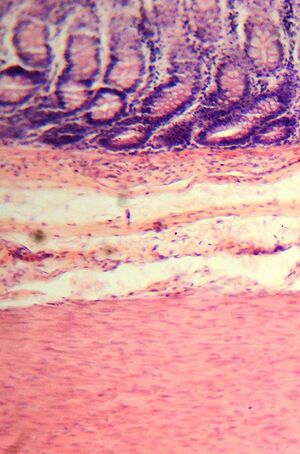

قطاع نسيجي.